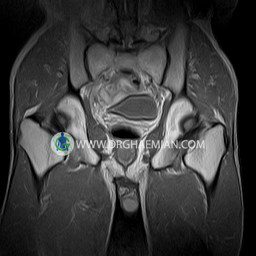

پزشکان اغلب از تصویربرداری ام آر آی برای تشخیص و درمان عارضه های پزشکی که فقط با استفاده از اشعه ایکس یا میدان مغناطیسی و امواج رادیویی قابل مشاهده است، استفاده می کنند. دستگاه ام آر آی تصاویر دقیق از ساختار های داخلی بدن ایجاد می کند. در این کیس استئومیلیت لگن، آتروز و سنیویت دیده می شود.

HIP JOINT MRI

( without contrast )

Technique : coronal STIR , coronal T2 , Axial T1 , axial T2 .

REPORT:

The femoral heads and acetabula are normal shape , signal intensity and the femoral heads are well covered by the acetabular margins .

The joint spaces are of normal width without fluid collection .

The articular surfaces are smooth and congruent and show normal cortical thickness .

Each femoral shaft has normal margins and contains a normal bone marrow signal .

The imaged muscles and the lesser pelvis show no abnormalities .

– Heterogeneous signal change (high T2/STIR , low T1) in proximal metaepiphysis of left femur without articular surface irregularity suggestive for bone bruise (stress fracture?), osteomyelitis & arthritis and marrow infiltration (less probable)

– Left hip joint effusion suggestive for synovitis

are seen.

COMMENT: Clinical correlation and MRI with contrast are recommended.